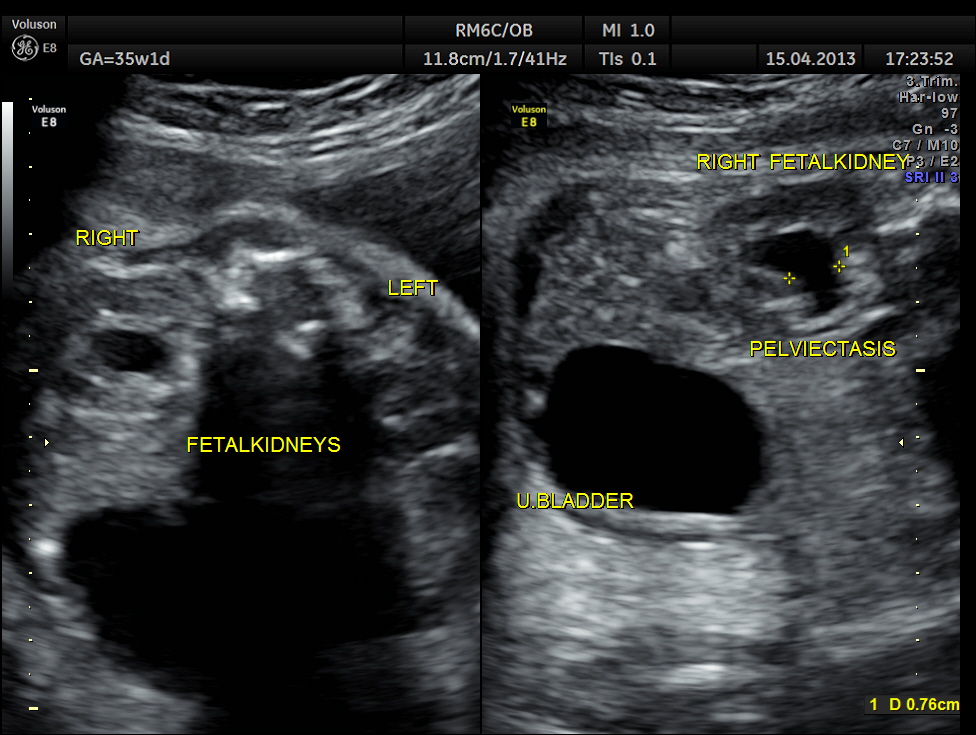

This was a 26-year-old lady with no history of consanguinity. The scan was done at 35 weeks of gestation.

Right fetal kidney shows mild pelviectasis.

Rt proximal ureter is mildly dilated

Right sided hydro uretero nephrosis , with likely obstruction at right vesico ureteric junction.